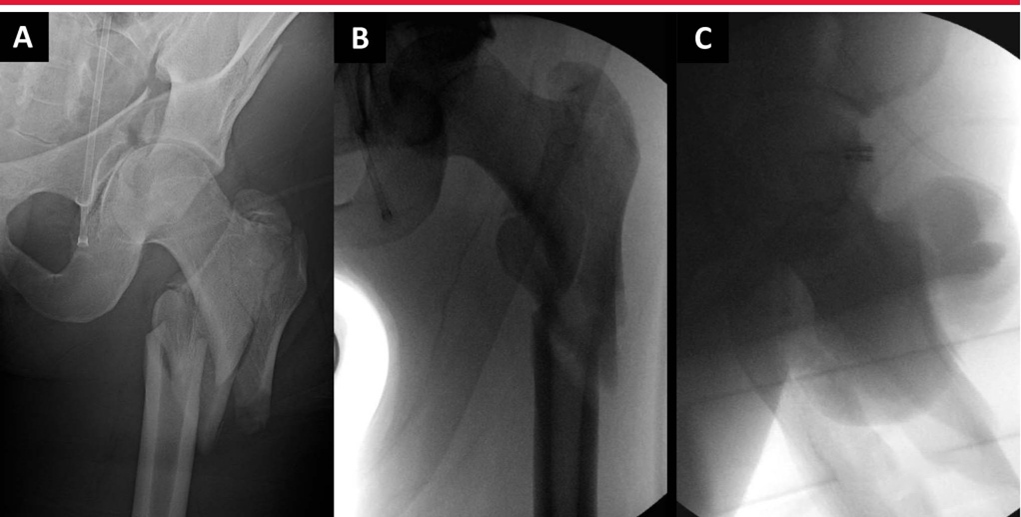

Интраоперационная боковая рентгеноскопия бедра для оценки репозиции и имплантата. А. Боковое изображение, наиболее подходящее для имплантата, демонстрирующее коллинеарность головки, шейки бедренной кости и оси бедренной кости. Б. Боковая рентгенограмма того же тазобедренного сустава во внутренней ротации. C: Повернутое наружу боковое изображение того же бедра, оптимальное для оценки переднемедиальной кортикальной поддержки и репозиции вертельных переломов. D–F: интраоперационные рентгеноскопические изображения, полученные в положении лежа на столе для переломов, показывающие вид в прямой проекции (D), боковой вид имплантата (E) и боковой репозиции (F).